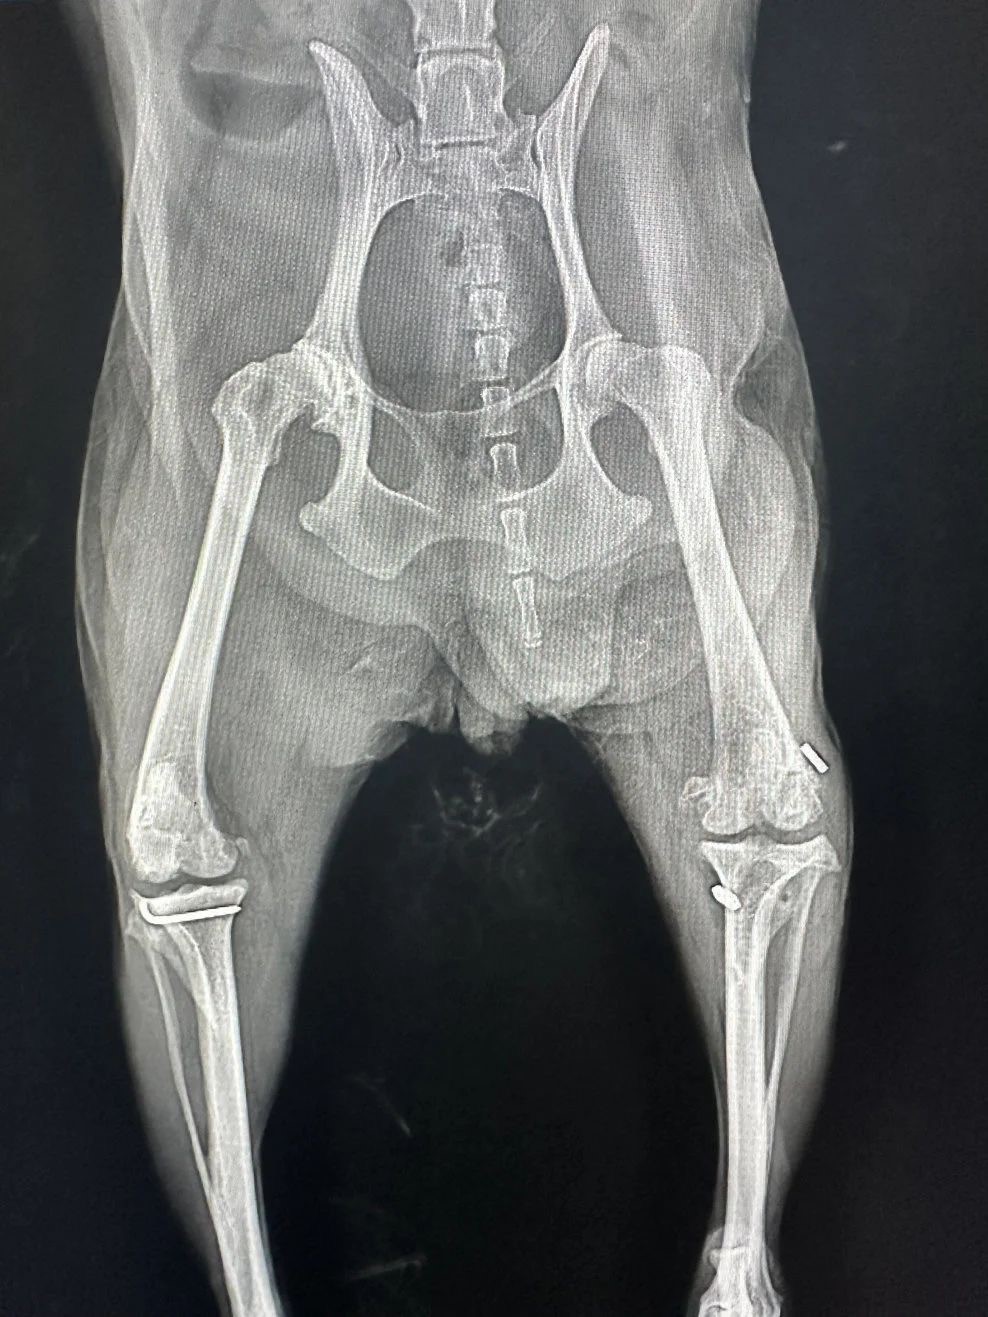

Figure 1. Pre-op X-ray